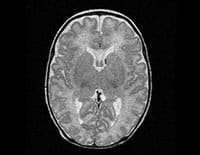

MR scans are vital to neonatologists who need precise data that might change a newborn’s course of care, such as the severity of brain damage after a traumatic birth. Because they do not use radiation, MR scans also present less of a health risk than other imaging technologies, especially in preterm infants whose systems are still developing.

An innovative, high-field magnetic resonance (MR) scanner designed by researchers at Cincinnati Children’s Hospital Medical Center could provide a safer way of performing imaging studies on critically ill and premature newborns. Currently in operation for investigational use in the Neonatal Intensive Care Unit (NICU), it is the only infant-sized MR scanner in the world housed within a NICU and the only one in the world designed specifically for infants.